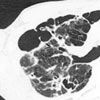

The white blood cell count was 13,900/µL; serum electrolyte levels were normal. A chest radiograph showed bilateral upper lobe infiltrates, nodules, and cavitary lesions. These findings were confirmed on a CT scan of the thorax (Figure 2).

Figure 2 – A CT scan of the thorax revealed subpleural blebs in the

upper lobes bilaterally with a cavity in the right upper lobe and infiltrates

in the left upper lobe.